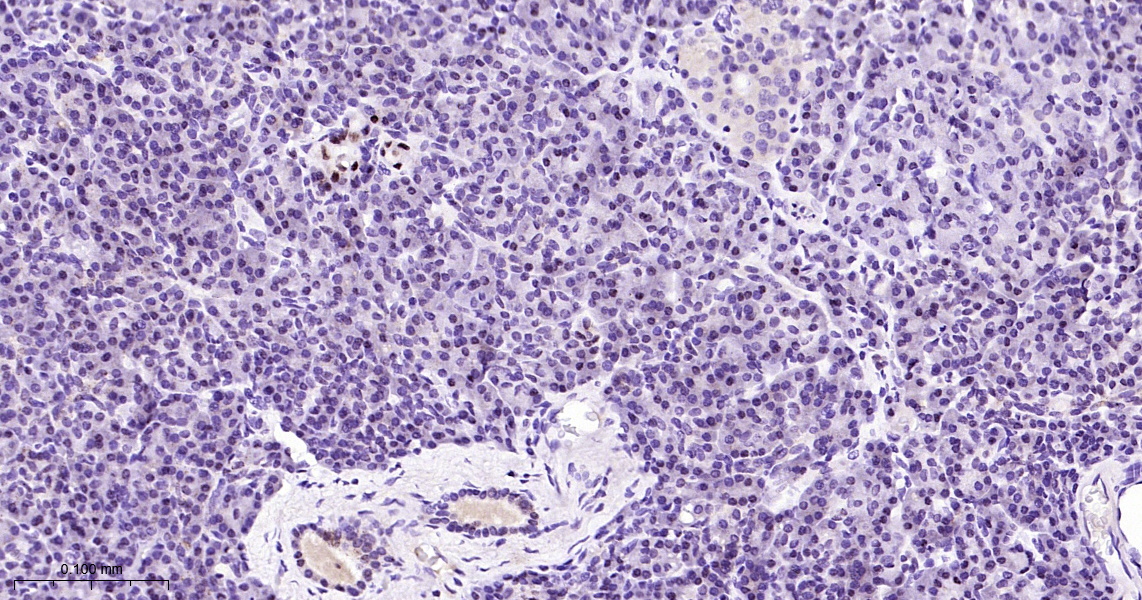

• IHC-P

IHC-P IHC-P1:50-200